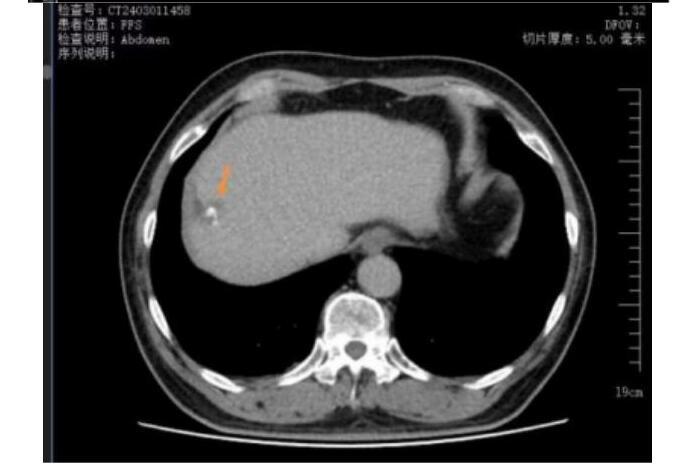

王先生(化名)65岁,2023年5月体检时发现肝占位,后行肝胆脾增强CT检查提示肝右叶富血供结节,径线约22mm*17mm,影像诊断考虑为肝恶性肿瘤,来到哈医大四院介入血管外科寻求进一步诊疗。患者行TACE术治疗后一周,接受了CT引导下冷冻消融治疗,术中患者疼痛轻微,术后患者恢复良好,三天后顺利出院。

术前上腹CT增强检查,考虑肝右叶恶性肿瘤